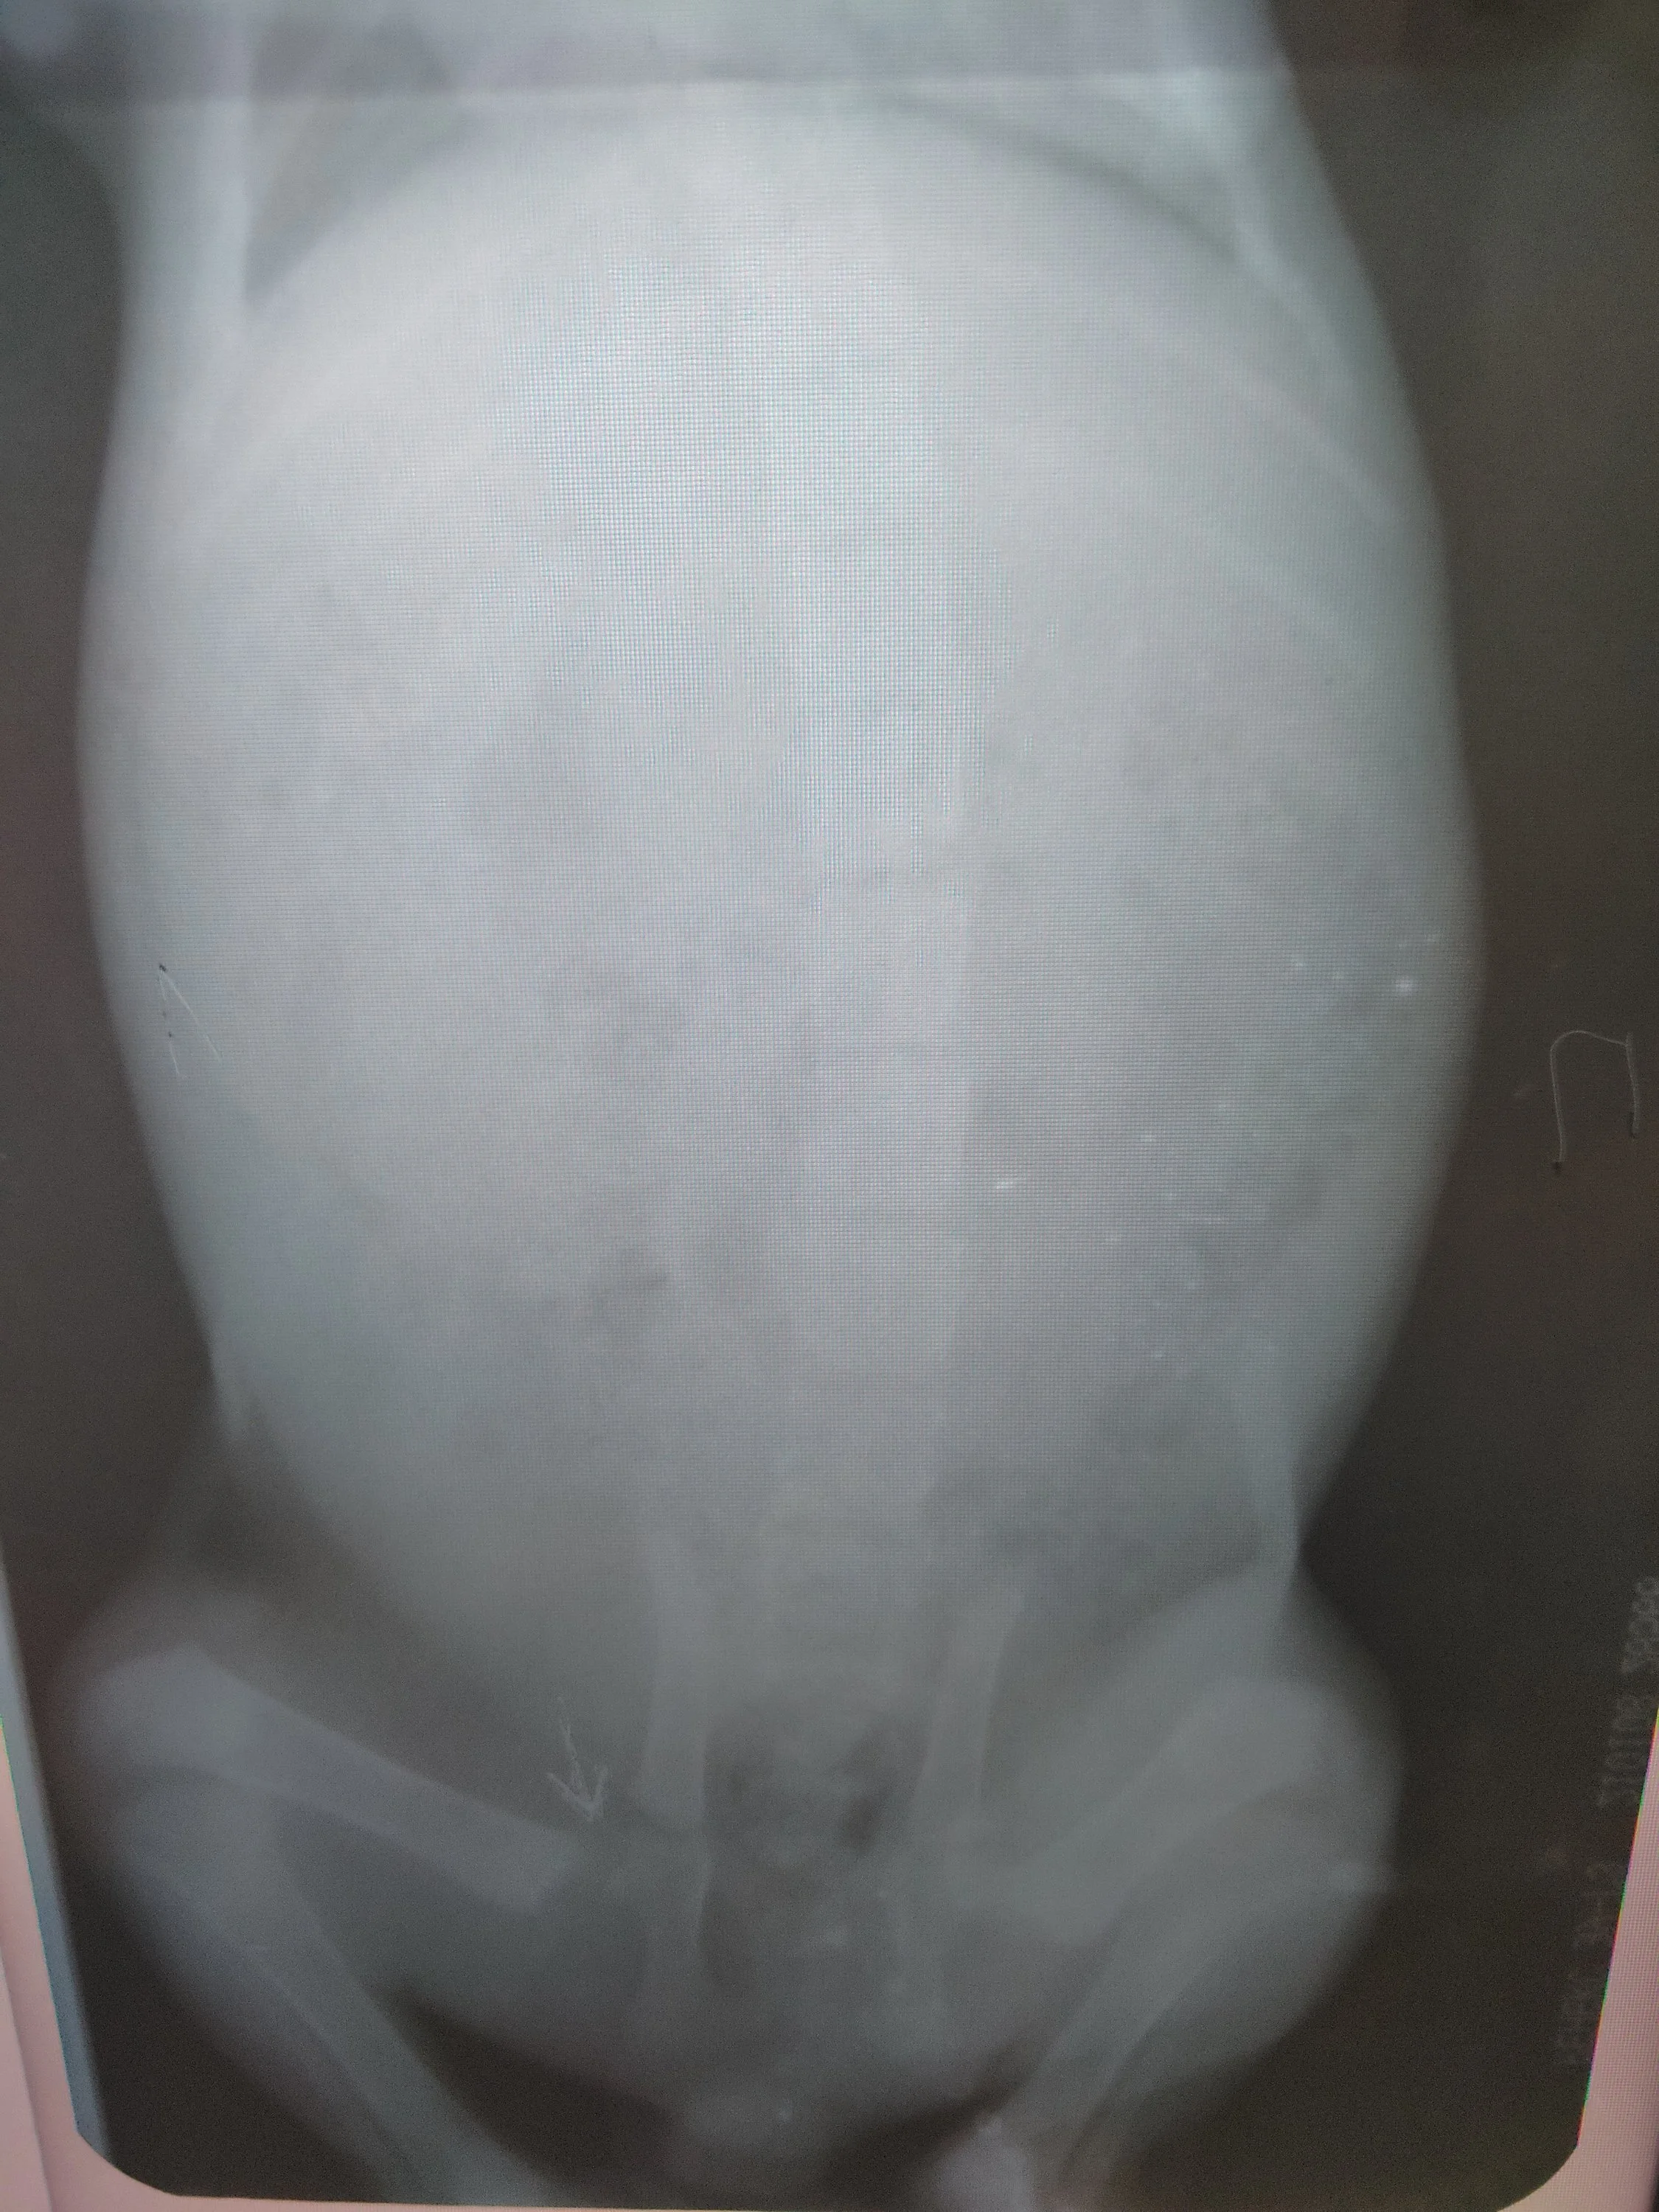

Начал хромать, повезли на рентген - перелом шейки бедра. Был до нас, начал срастаться, но т.к. мы были не в курсе, от слишком активных игр костная мозоль снова сломалась.... Снимок даже покажу.

IMG_20200910_192008.webp

В общем, ортопед велел купить клетку и ево туда посадить на месяц. Купили. Сидит. Дальше врач скажет, нужна операция или срастется перелом.